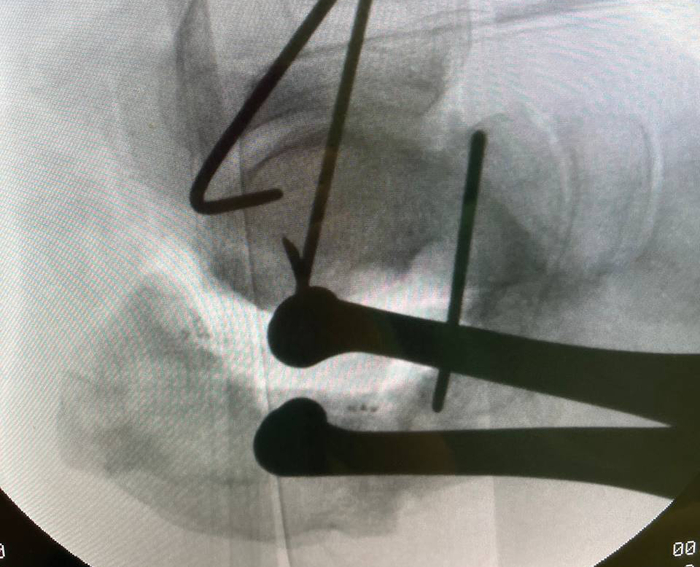

Подобным образом выглядит ЭОП-снимок на этапе удаления металлоконструкции и склерозированной кости. Можно видеть силуэт дистрактора Хинтермана, который я использовал на данном этапе для временной дистракции подтаранного сустава, чтобы обеспечить лучшую визуализацию. Мы видим насколько уменьшился объем пяточной кости по сравнению с первоначальном этапом. Это результат резекции в пределах жизнеспособной кости. Жизнеспособность кости оцениваю исключительно макроскопически по наличию губчатой структуры и кровяной расы (да, под жгутом она тоже есть).

Этапный снимок с установкой аппарата.